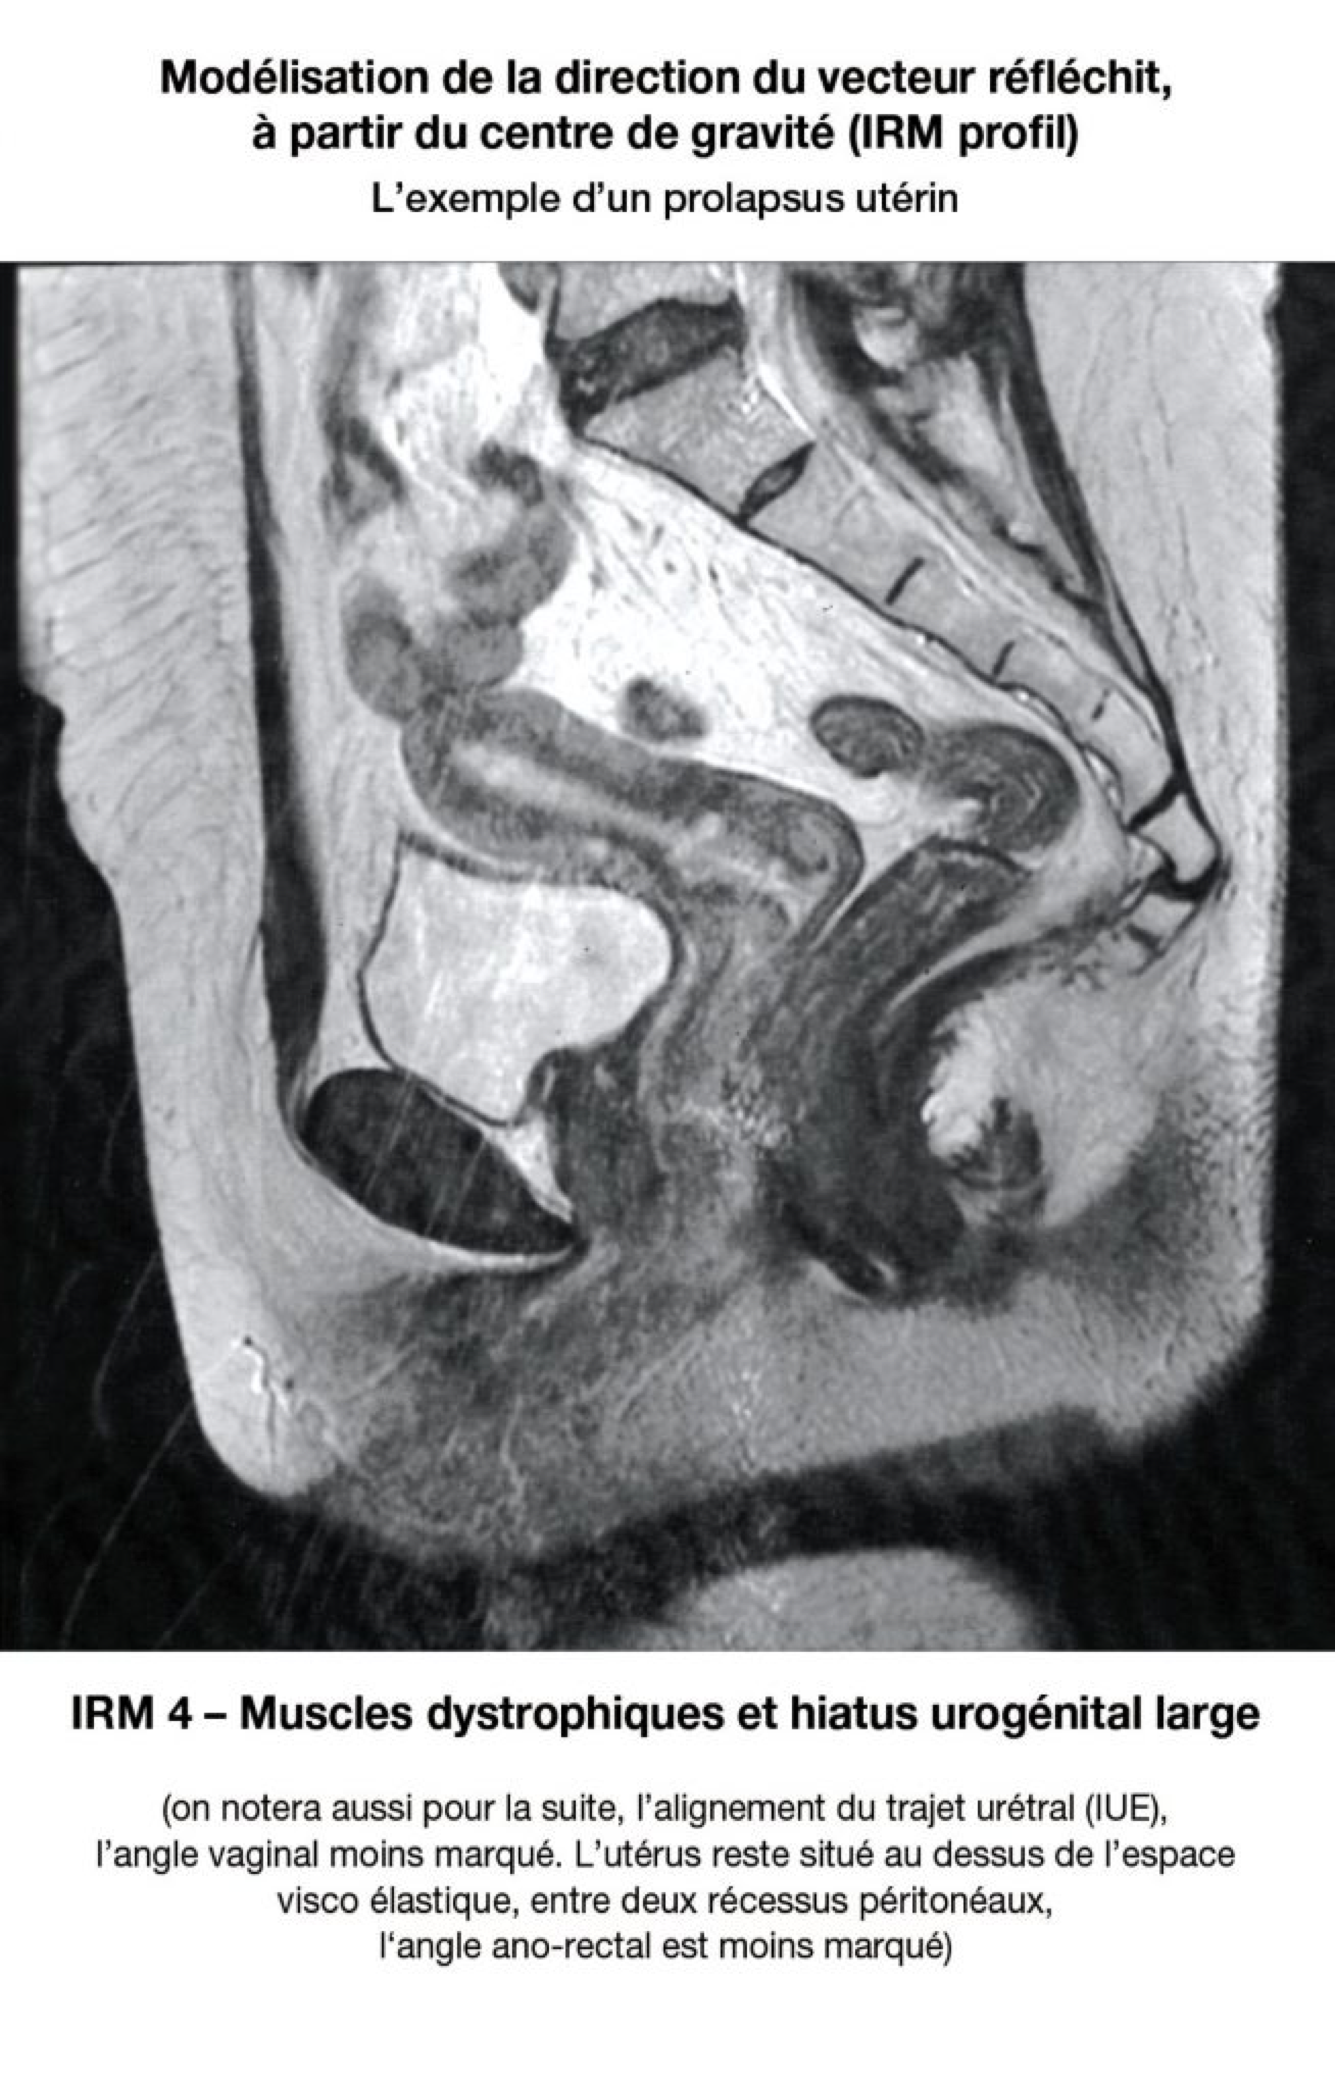

9. Périnée prolapsus

LE VECTEUR DE LA PRESSION ABDOMINALE S'ÉCHAPE À TRAVERS LE HIATUS UROGÉNITAL

Le « vecteur résultant » des forces gravitationnelles et abdominales va être renvoyé plus ou moins haut, plus ou moins bas, selon que ces muscles seront épais (femme jeune - centre de gravité élevé), ou seront atrophiques ou délabrés (centre de gravité abaissé).